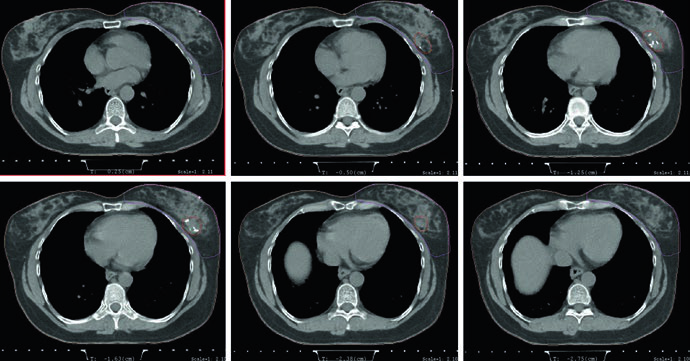

Tomografia de simulação, posição supina, prona e DIBH

Na simulação para mama inteira, o capítulo recomenda tomografia com espessura de corte menor ou igual a 3 mm, em posição supina ou prona. Para APBI, a exigência fica mais estreita: cortes de 1,5 a 2 mm através da cavidade de lumpectomia podem melhorar a definição desse volume. Não é um detalhe burocrático. É a diferença entre aceitar uma cavidade apenas presumida e enxergar melhor o alvo que depois orientará a expansão de CTV e PTV.

Quando a opção é pelo setup supino, a paciente deve ficar em prancha mamária com os braços acima da cabeça. Se o tumor é à esquerda, o texto recomenda considerar respiração profunda em inspiração mantida, a técnica de DIBH, para reduzir a dose no coração. O verbo usado importa. O capítulo não transforma DIBH em ritual obrigatório para todos os casos à esquerda, mas deixa claro que a redução da dose cardíaca deve entrar no raciocínio do planejador sempre que esse recurso estiver disponível e for reproduzível.

A posição prona ganha um espaço amplo e bem delimitado. Pacientes com mamas pendulares podem se beneficiar dela porque a separação diminui e a homogeneidade do tecido no planejamento melhora, algo que pode reduzir toxicidade aguda. O texto ainda aponta duas consequências dosimétricas: menos radiação no pulmão e possibilidade de evitar melhor o coração. Só que os autores fazem a ressalva que interessa à prática: se o leito tumoral encosta na parede torácica, o coração pode paradoxalmente se aproximar do campo de tratamento. O capítulo não vende a prona como solução automática; ele a apresenta como ferramenta útil, desde que o caso seja lido com cuidado.

Há também disciplina mecânica no setup prono. A paciente deve ser colocada em uma prancha dedicada para mama, e o conforto precisa ser garantido porque a reprodutibilidade depende disso. O texto fecha esse bloco lembrando que lesões ortopédicas no dorso ou no pescoço podem tornar a prona uma má escolha. É um ponto simples, mas clínico. O melhor arranjo geométrico perde valor se a paciente não consegue reproduzi-lo ao longo do tratamento.

Essa comparação entre supino e prono conversa diretamente com o planejamento das figuras. O exemplo em prono usa tangentes com field-in-field, a mesma prescrição de 42,4 Gy em 2,65 Gy por fração e boost com mini-tangentes fotônicos até 10 Gy em 2,5 Gy por fração. A legenda ainda acrescenta um detalhe anatômico que serve de guia: a borda posterior do campo deve incluir parte do músculo peitoral. Para quem quiser avançar do raciocínio da mama inicial para cobertura regional, vale continuar a leitura no nosso artigo sobre irradiação nodal regional no câncer de mama.